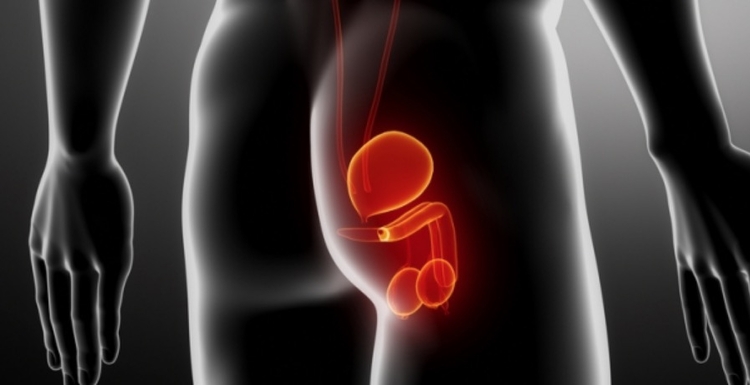

A Hiperplasia é o aumento do número de células em determinado tecido, neste caso, na próstata (prostática). A próstata é uma glândula presente no organismo masculino, do tamanho de uma noz e responsável pela produção do líquido seminal. A HPB normalmente se inicia em homens com mais de 40 anos e quando se associa a sintomas do trato urinário inferior (LUTS) pode provocar grande impacto na qualidade de vida.

1. O aumento do volume da próstata é uma condição comum conforme os homens envelhecem?

Verdade

4. Jato fraco, pode ser próstata aumentada

Verdade